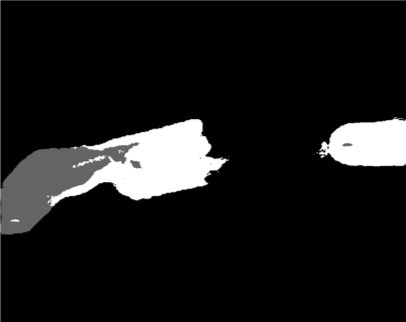

Our challenge was made up of 3 sub-problems. The first was binary instrument segmentation, where each frame was separated into da Vinci Xi instruments and a background class, which contained an ultrasound probe, surgical clips and porcine tissues. The second task was instrument part segmentation, where we scored the participants on whether they could correctly segment each articulating part of the instrument (see Fig. 3). Our final task was to segment and classify the instruments (see Fig. 4).

We provided the first 225 frames of 8 sequences as training data and kept the last 75 frames of those 8 sequences as test data. 2 of the full 300 frame sequences were kept as test sequences. Test labels were kept hidden from the participants. Our datasets contain 7 different robotic surgical instruments. The Large Needle Driver, Prograsp Forceps, Monopolar Curved Scissors, Cadiere Forceps, Bipolar Forceps, Vessel Sealer and additionally a drop-in ultrasound probe, which is typically held in the jaws of the Prograsp Forceps instrument. Samples from the training datasets are depicted in Fig. 2 and examples of the different instrument types are shown in Figure 3 and 4.